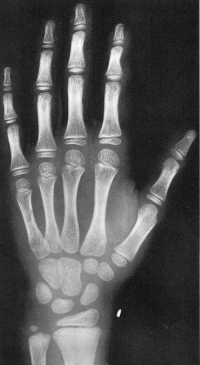

Sexo Masculino

2 anos

Sexo Feminino